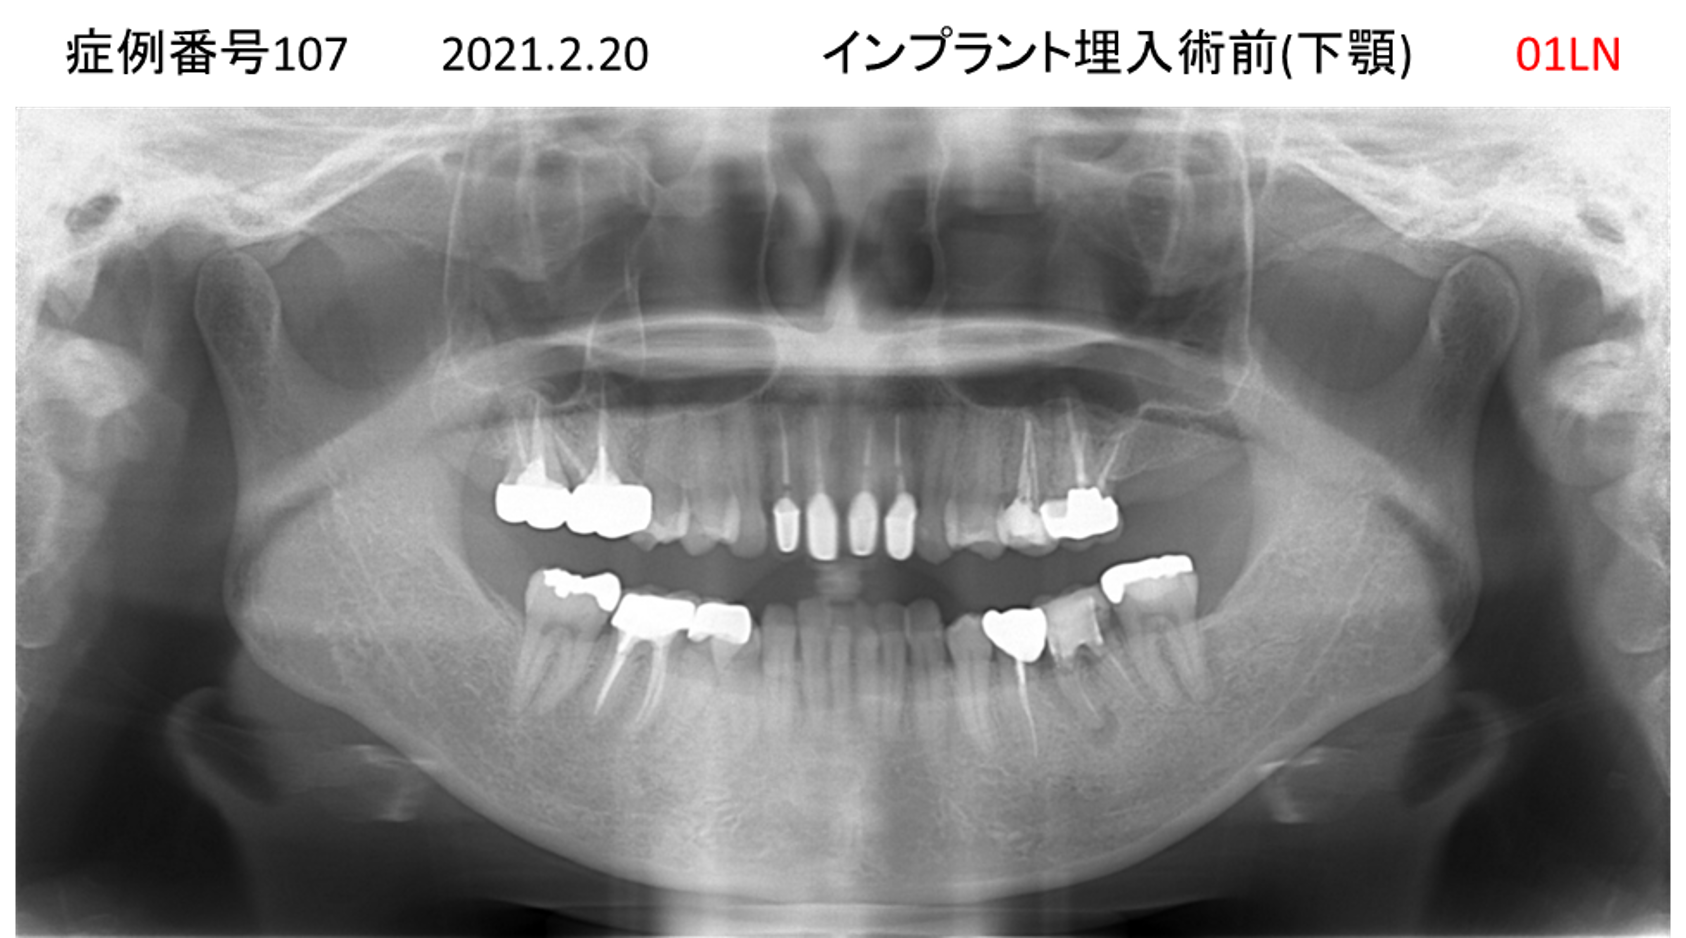

全く噛めない患者様のインプラント症例

| 治療名称 |

インプラントAGC |

| 治療費用 |

860万円+税 |

| 治療期間 |

12か月 |

| 患者さんの症状(主訴) |

全く噛めない、ごはんが後もに食べられるようになりたい、人前で口元を隠したくない |

| 治療内容 |

サイナスリフト、GBR、インプラント、AGC |

| 治療結果 |

しっかり噛めて踏ん張ることができる。食べ物をを選ばなくて済む、何でも食べられる、体重が増えた。見栄えがきれいすぎて自分じゃないみたい |

| 治療の注意点(リスク/副作用) |

インプラントが壊れたら再治療が必要 |